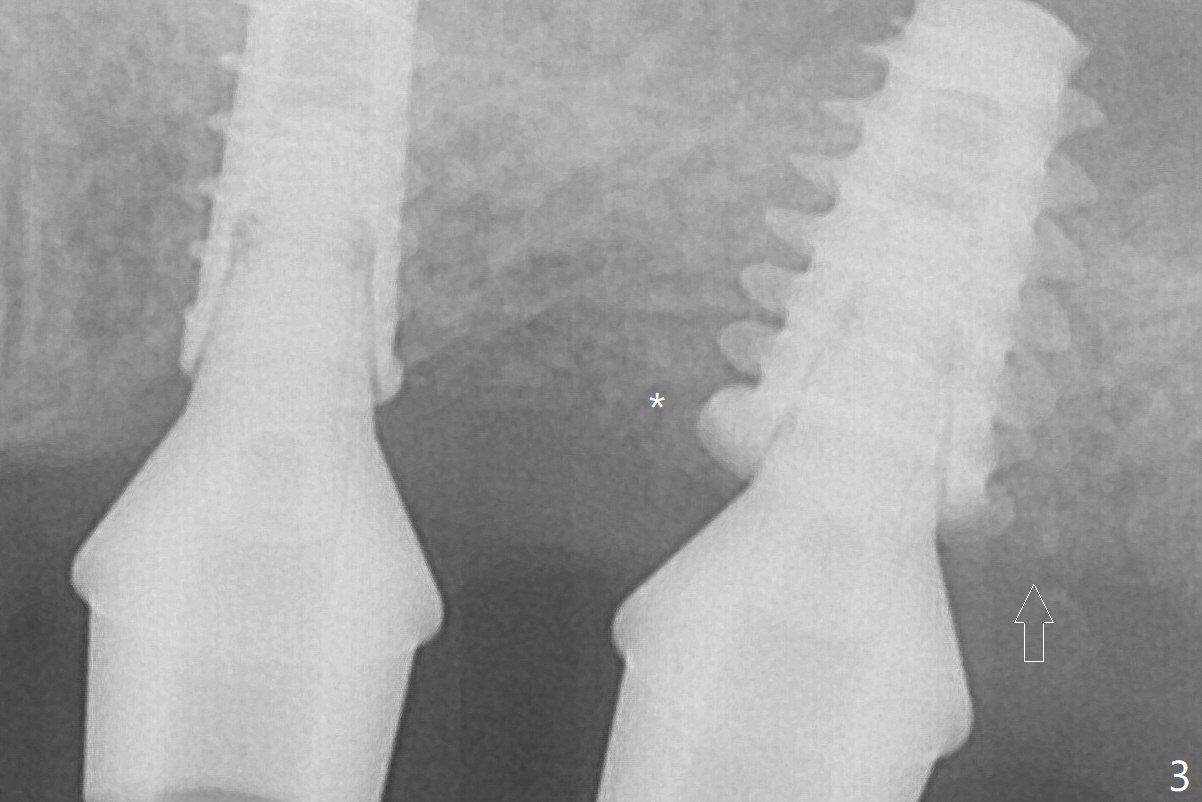

After adjustment of trajectory, a 4x11 mm definitive implant is placed at #14 with ~ 35 Ncm, while a 6x9 mm implant is placed at #15 with ~35 Ncm (Fig.2 (*: Vanilla Graft with Osteogen)).  The patient returns 3 months postop (Fig.3).  After changing abutments to 5.5x5.7(3) mm, impression is taken.  While there is distal bone resorption (arrow (due to the large abutment/pressure?)), the mesial bone graft retains (*).